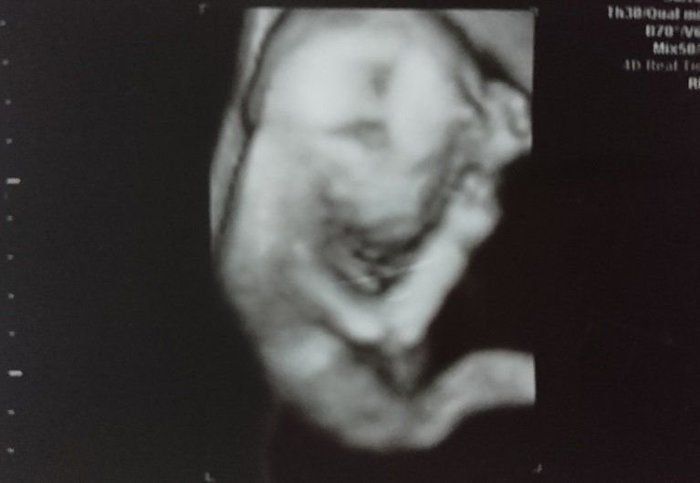

くろみつさんの妊娠18週目のエコー写真 男の子と判明し、「タロー」と命名

上半身の4D画像です。右手を頭に、左手を頬に置いている姿がなんともかわいらしく映っています。性別が男の子とわかったので「タロー」と命名。声に出すのは恥ずかしかったので、心の中で「タロー」と話しかけていました。つわりが終わったためか、食欲が湧いてきて、体重増加が気になりだしました。安定期に入り、お散歩を長めにしたり、プールで泳いだりもしていました。